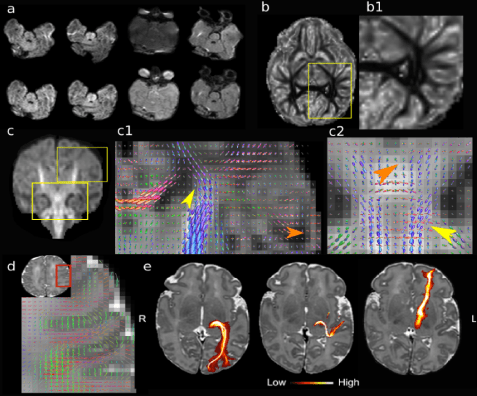

Time-efficient and flexible design of optimised multi-shell HARDI diffusion

Hutter, J, Tournier, JD, Price, AN, Cordero-Grande, L, Hughes, EJ, Malik, S, Steinweg, J, Bastiani, M, Sotiropoulos, SN, Jbabdi, S, Andersson, J, Edwards, AD & Hajnal, JV 2017, Magnetic Resonance in Medicine. DOI: 10.1002/mrm.26765

Quiet echo planar imaging for functional and diffusion MRI

Hutter, J, Price, AN, Cordero-Grande, L, Malik, S, Ferrazzi, G, Gaspar, A, Hughes, EJ, Christiaens, D, Mccabe, L, Schneider, T, Rutherford, MA & Hajnal, JV 2017, Magnetic resonance in medicine. DOI: 10.1002/mrm.26810